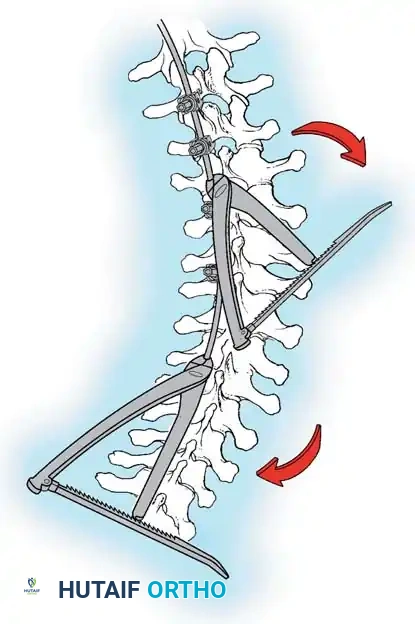

The Hall Technique

The Hall technique offers an alternative method for facet obliteration and grafting, particularly useful in rigid deformities.

Fig. 38-28: The Hall technique of facet fusion, involving sharp excision of the inferior facet and trough creation.

- Sharply amputate the inferior articular facet with a gouge and remove the bone fragment entirely. This exposes the cartilage of the superior facet.

- Remove the exposed cartilage completely with a sharp curet.

- Create a bleeding trough by removing the outer cortex of the superior facet.

- Impact cancellous bone grafts directly into this vascularized trough.

- Complete the procedure with global decortication of the posterior elements.